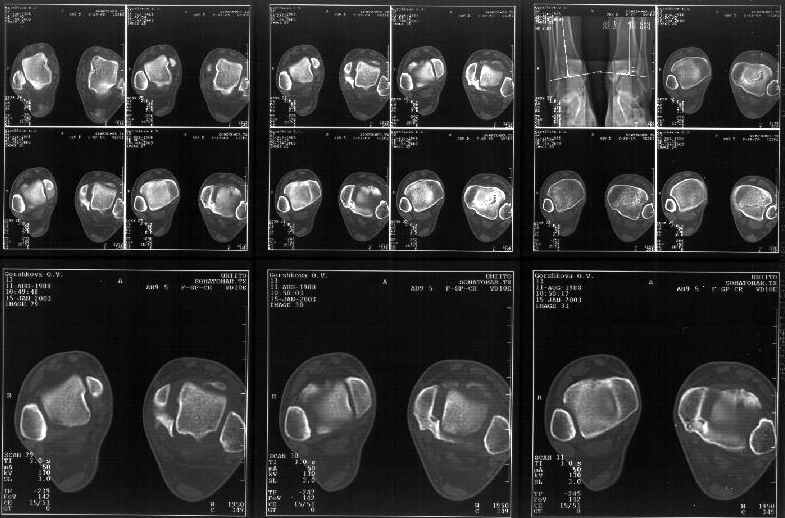

Мне в тоже время совершенно ясно видно по той же КТ, по 4 срезам, расположенным в центре и вверху пленки, что перелома внутренней лодыжки не было, в следующем собщении я приложу увеличенный фрагмент томограммы. А к этому письму прилагаю увеличеный фрагмент послеоперационной рентгенограммы, где выделил отколотый фрагмент

позади внутренней лодыжки. И он, как я вижу, находится между стержнем и тараном. А перелома внутренней лодыжки, и тем более смещения, IMHO

не определяется.

Отправитель: Alexander Chelnokov 12 Январь 2003, 14:55

> направлениях.Отдавил и отломал переднюю часть мед. маллеолюса от его

> тибиальной основы. По мне, КТ это совершенно ясно показывает.

Здесь 4 среза, начиная от основания лодыжки и проксимальнее. Где, по Вашему мнению, проходит линия перелома, отделяющая переднюю часть внутренней лодыжки от большеберцовой кости? Заранее спасибо.

Я пометил линию перелома черной линией.

К сожалению на последних присланных срезах КТ нет более низкого, через таран, среза, который был на прежнем майле. На XR я попытался показать

стержень внутри сустава и то как он раскрывает пространство между тараном и мед. малеолом.

Сегодня пациентке сделали сравнительную КТ. А ксиальные и Фронтальные срезы приложены. Ваше мнение?

Фронтальные

Аксиальные

На КТ я попытался изобразить скромными своими способностями (А)- место перелома, (С)- нормальный суставной зазор меж тараном и тремя его маллеолами. (В)- образовавшийся в результате перелома широкий раза в три зазор, позволяющий, по-моему, сублюксацию тарана при ходьбе. В свете данных КТ, критически важных, я бы предложил вертикальную остеотомию места перелома

задне-внутренним подходом и фиксацию мед. маллеола прижатым к тарану с помощью тонкого compression screw. После этого гипсовый сапожок и немедленное расхаживание ноги.